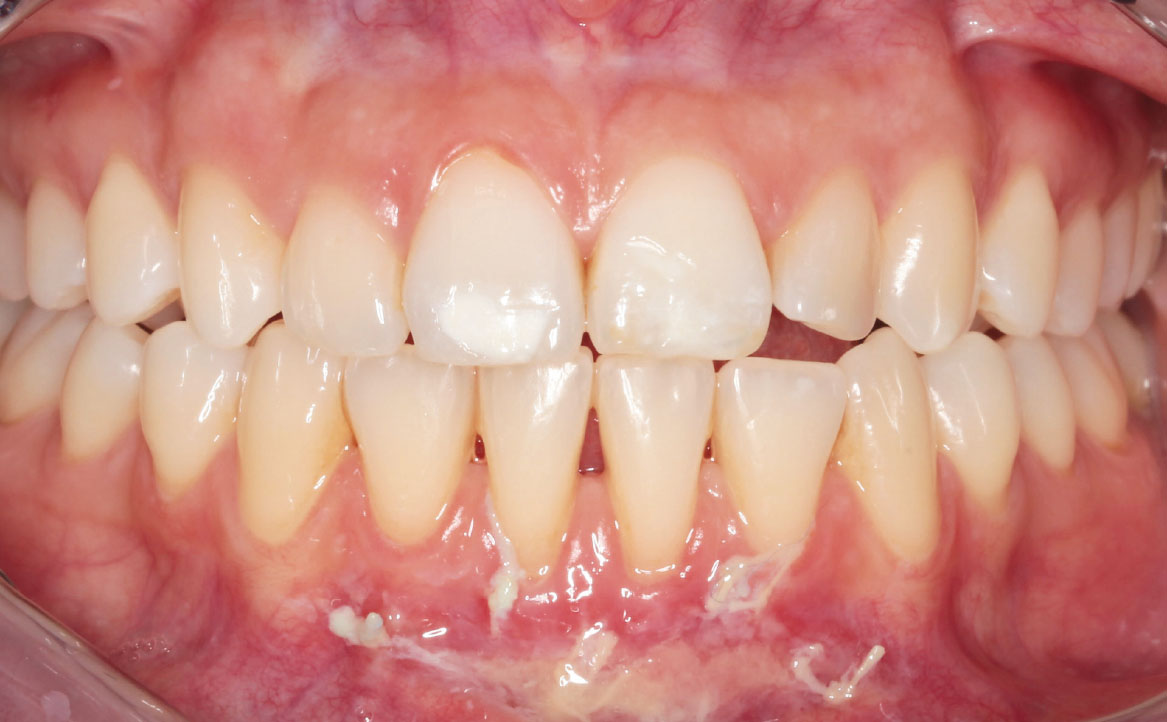

A una settimana dall’intervento si osserva un principio di guarigione della ferita: il sito appare completamente rivestito di fibrina e privo di segni di infiammazione (fig. 11, 12).

Al follow-up a un mese dalla vestibuloplastica, si osserva la completa riepitelizzazione del sito chirurgico (fig. 13, 14). Si riscontra la presenza di una piccola area esofitica, dovuta al mancato riassorbimento di uno dei punti di sutura applicati.